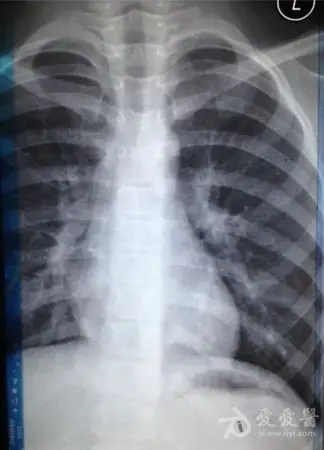

请教:6岁,胸片上肺炎,站立位和躺着拍的范围为什么不一样呢